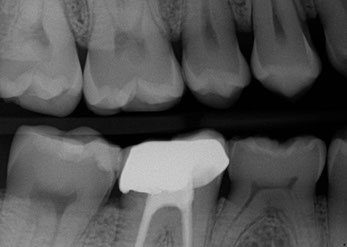

HD Digital X-ray Fillings & Crown